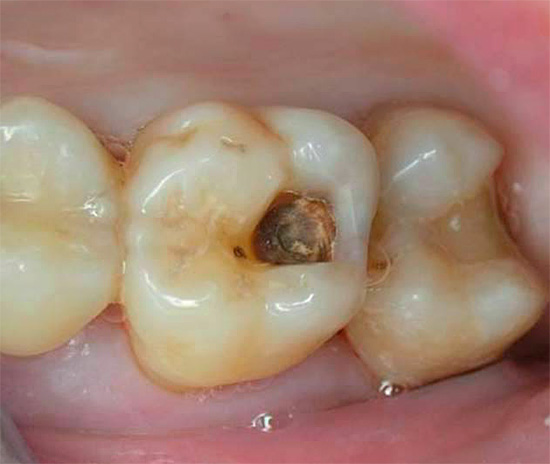

La foto sotto mostra un esempio di carie profonde, in cui la camera pulpare del dente è già molto probabilmente interessata:

La seguente foto mostra un esempio di una cavità così profonda e cariata: